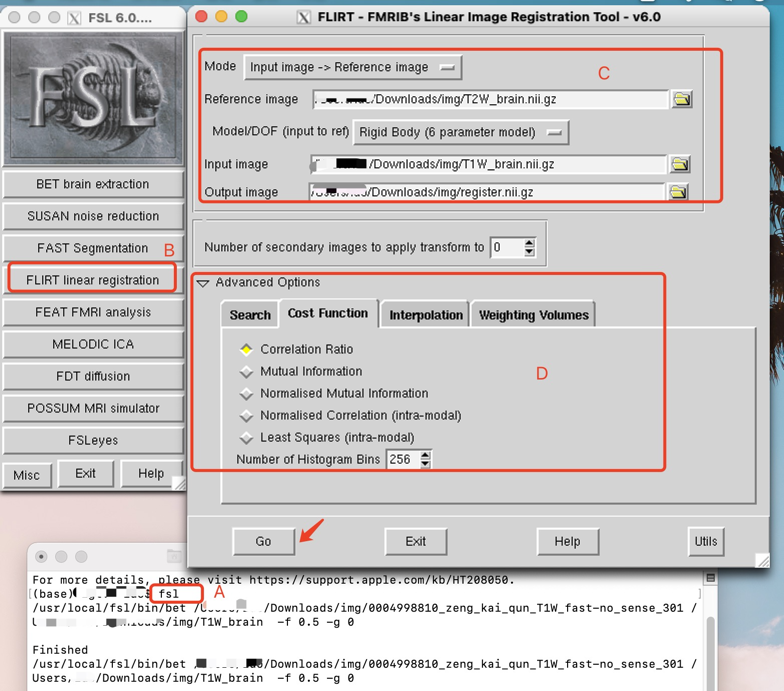

使用图像界面配准如下:

先打开fsl > 点击B按钮,出现CD区,在C中输入 reference image(我的T2w对比度好些,用它做参考图像), DOF(自由度)选择刚体变换,6个自由度。设置输入输出图像地址。D区中的高级选项可以设置代价函数和插值方式,这里我用默认的就行。 -